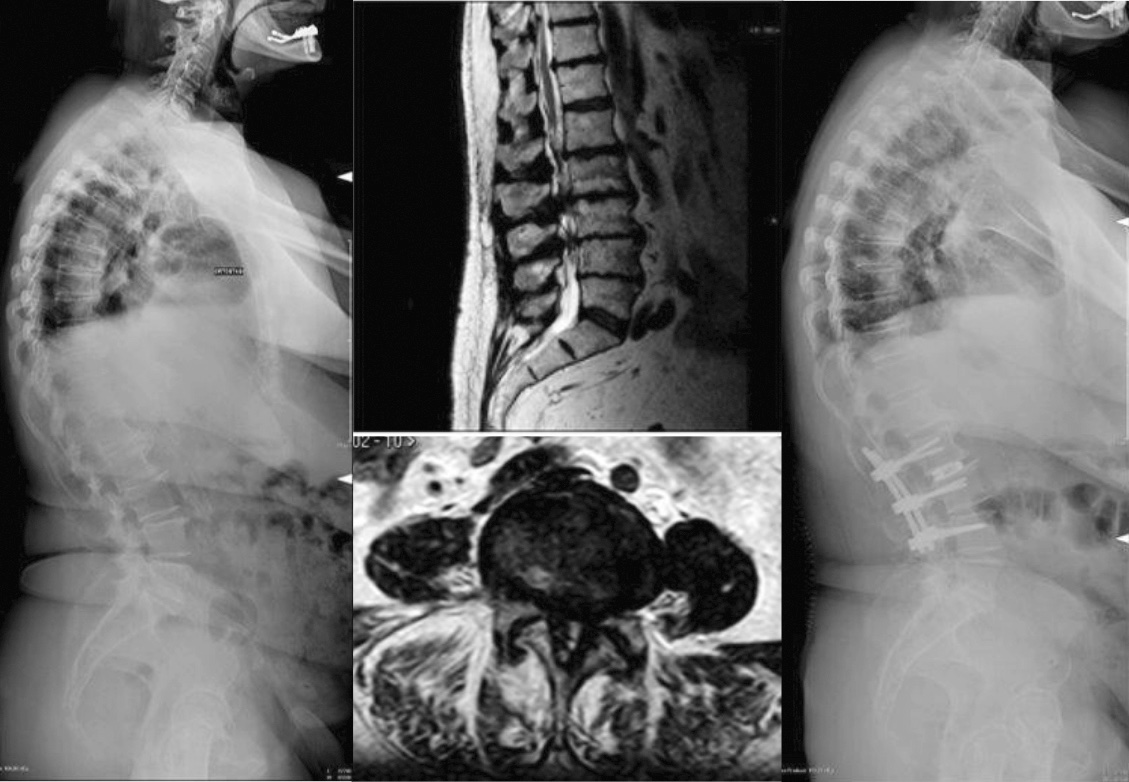

Tipicamente, un paziente bilanciato grazie all’arruolamento di meccanismi di compenso può presentarsi con un esteso spettro di manifestazioni cliniche. In primo luogo, il paziente può lamentare una sintomatologia centrale e/o periferica, legata unicamente alla patologia di base che ha richiesto l’instaurarsi dei compensi. In questa situazione, il paziente può essere gestito inizialmente conservativamente, intraprendendo un trattamento fisioterapico riabilitativo mirato ad ottimizzare i meccanismi di compenso, sfruttando il loro potenziale funzionale residuo. Parallelamente, risulta appropriato impostare una terapia farmacologica basata sulla sintomatologia riferita dal paziente. Possono infatti essere utilizzate diverse associazioni di farmaci antiinfiammatori non steroidei (FANS) o analgesici nelle forme lievi, nelle forme moderate possono essere aggiunti farmaci ad azione decontratturante, e nelle forme severe associate a dolore periferico possono essere utilizzati neurotrofici, corticosteroidi e FANS, gli ultimi sostituiti dopo 10 g da un analgesico centrale. In caso di fallimento del trattamento del trattamento conservativo, può essere preso in considerazione l’intervento chirurgico, sempre focalizzato sulla sintomatologia del paziente: tipicamente vengono eseguite decompressioni centrali e foraminali, associate ad artrodesi che rispettino il compenso sagittale globale del paziente (Fig. 1).

In caso in cui il paziente fosse candidabile alla chirurgia, è imprescindibile un’attenta tipizzazione delle caratteristiche della singola deformità, in termini di raggio di curvatura e di rigidità, col fine di individuare la strategia correttiva più appropriata. In particolare, deformità ad ampio raggio e/o flessibili, possono essere dominate tramite osteotomie della colonna posteriore (di tipo Ponte e Smith-Petersen), eventualmente multiple, cercando di dissipare la correzione su ogni singolo livello. In caso di deformità a breve raggio e/o rigide, risultano necessarie aggressive osteotomie tricolonnari, come la PSO (osteotomia di sottrazione peduncolare) e la VCR (vertebrectomia). Le osteotomie tricolonnari, in ragione del loro importante potenziale correttivo, della loro alta complessità e degli elevati rischi che comportano, vengono eseguite tipicamente mono-livello, all’apice della deformità. Solo in rari casi, in cui il potenziale correttivo di una singola osteotomia tricolonnare non fosse sufficiente a ristabilire un corretto bilanciamento globale, è possibile eseguire osteotomie tricolonnari multilivello (Fig. 2) 6.